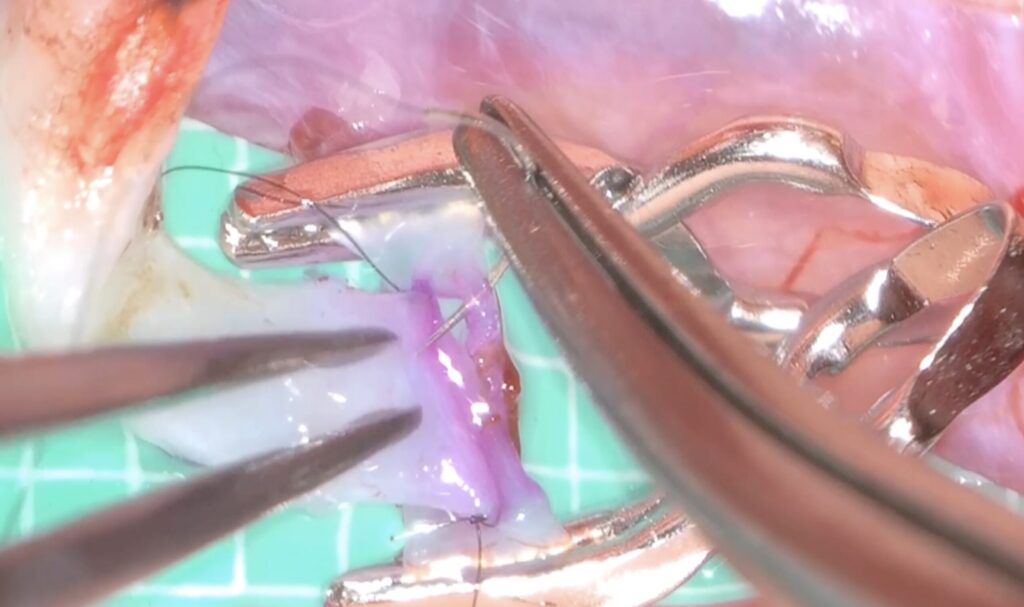

外視鏡を用いると吻合時にはデジタルズームをフットスイッチで入れると瞬時に高拡大にできます。

糸が通ったら、また瞬時にデジタルズームを切ります。